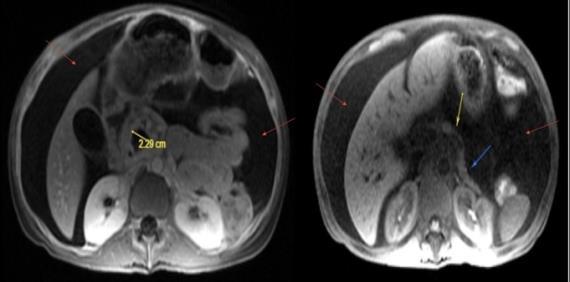

CASE PRESENTATION: A 67-year-old male with a history of partial liver resection, peptic ulcer disease, and Helicobacter pylori gastritis s/p quadruple therapy presented with acute on chronic abdominal pain despite being on a proton pump inhibitor (PPI). He had abdominal pain for the past 5 years associated with nausea, vomiting, diarrhea, and a 50-pound unintentional weight loss. An esophagogastroduodenoscopy (EGD) six months ago demonstrated peptic ulcer disease and Helicobacter pylori which was successfully eradicated.

He underwent a CT-abdomen/pelvis with intravenous contrast in the emergency department which revealed an enhancing 3.4 cm mass in the head of the pancreas with retroperitoneal lymphadenopathy. MRI of the abdomen confirmed the presence of a 3.2 cm enhancing pancreatic head mass with direct extension into the second portion of the duodenum and multiple enlarged retroperitoneal lymph nodes. EGD was remarkable for edema and granularity in the first portion of the duodenum. Endoscopic ultrasound (EUS) was notable for a hypoechoic and heterogeneous irregular mass in the pancreatic head measuring 25 mm by 23 mm in maximal crosssectional diameter with invasion into the serosa and muscularis mucosa of the duodenum. Fine needle aspiration of the pancreatic mass for cytology revealed a well-differentiated pancreatic neuroendocrine tumor (Ki-67 index <1%). Gastrin levels were ordered. He presented again to the hospital 3 weeks later with worsening epigastric abdominal pain and nausea despite adhering to PPI therapy. CT-abdomen revealed new proximal duodenal ulcerations. Gastrin level from the prior admission was noted to be 1988 pg/mL. He subsequently underwent a Whipple's procedure with no complications and was discharged home with a planned EGD surveillance in 6 months.

CONCLUSION: Establishing a diagnosis of ZE can be difficult due to the lack of consistent diagnostic criteria, the widespread use of PPIs that masks mask the symptoms and limited access to gastric pH testing. In our case, the diagnosis was based on a fasting serum gastrin level, FNA results, and imaging findings. Owing to its variable clinical presentation, high mortality, and challenging primary lesion identification, clinicians should consider ZE in the differential diagnosis of patients who are symptomatic despite taking PPI, having Helicobacter pylori successfully eradicated or having multiple duodenal and gastric ulcers that fail to respond to therapy.

Figure 1: CT Abdomen and Pelvis with contrast showing a suspicious mass in the second portion of the duodenum/pancreatic head.